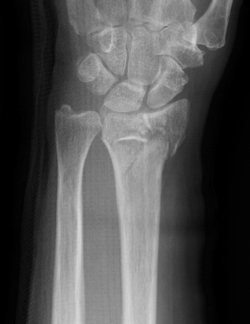

【橈骨遠位端骨折のX線像】

正面像

側面像